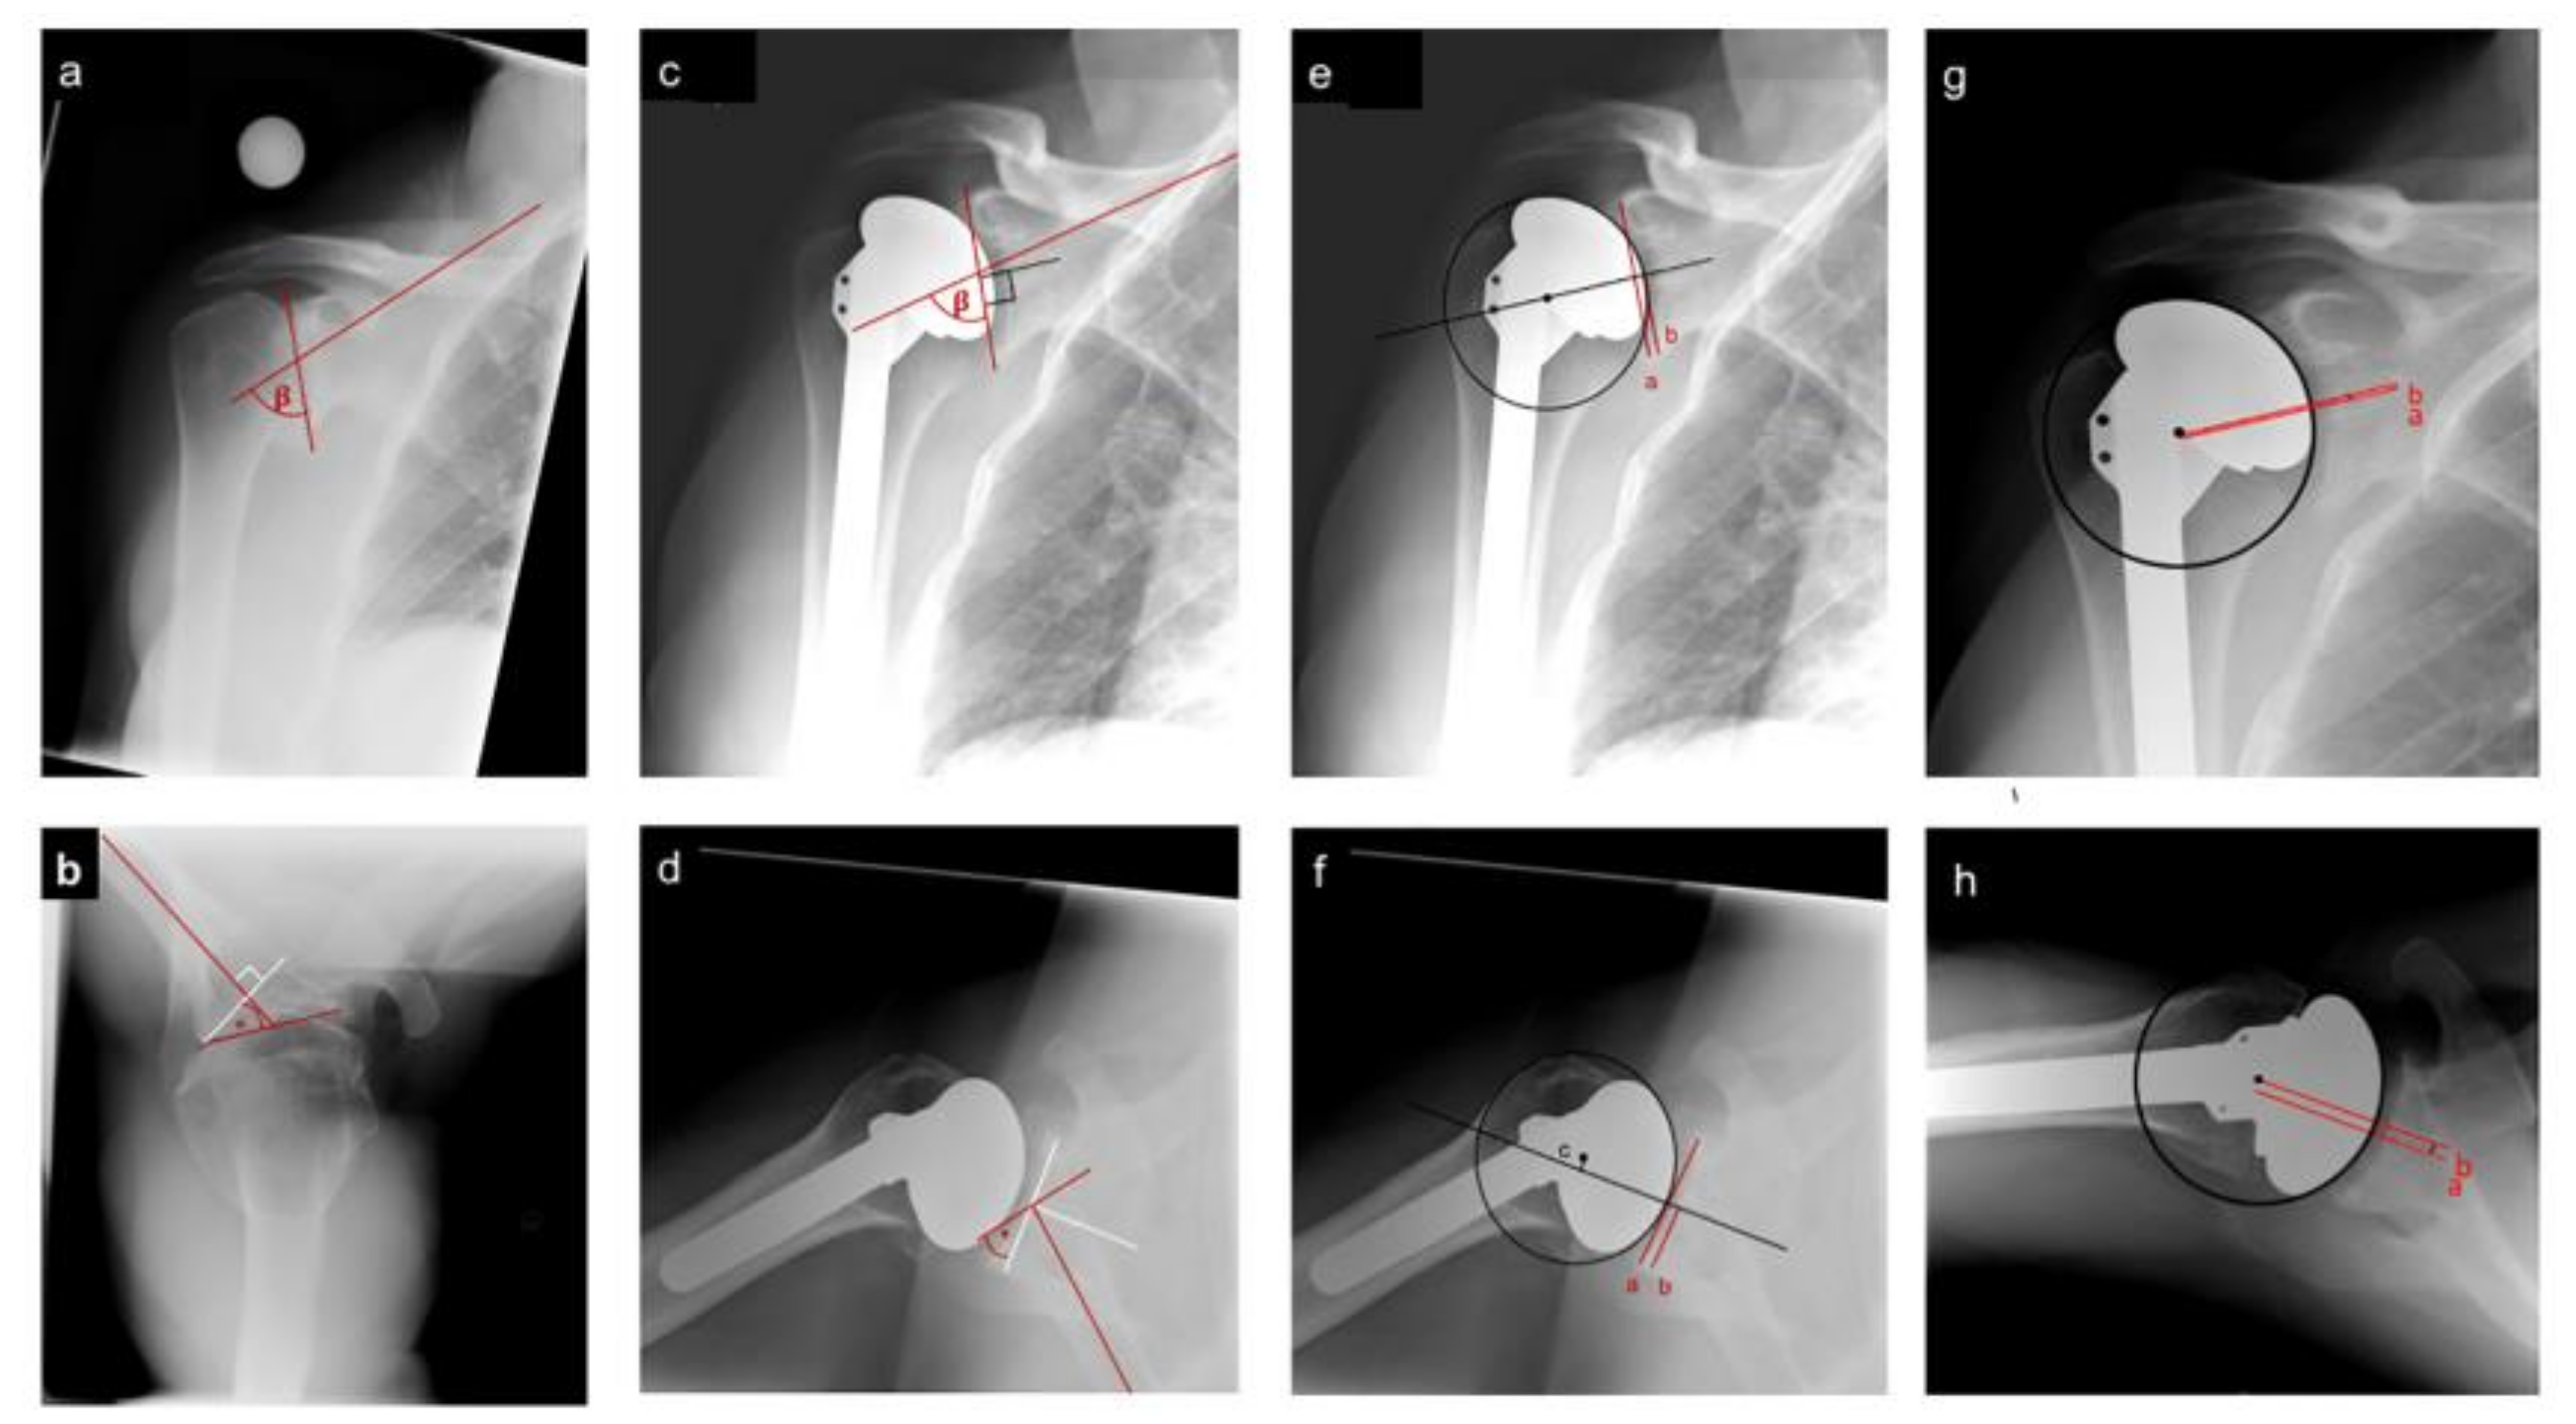

2.2. Radiographic Measures